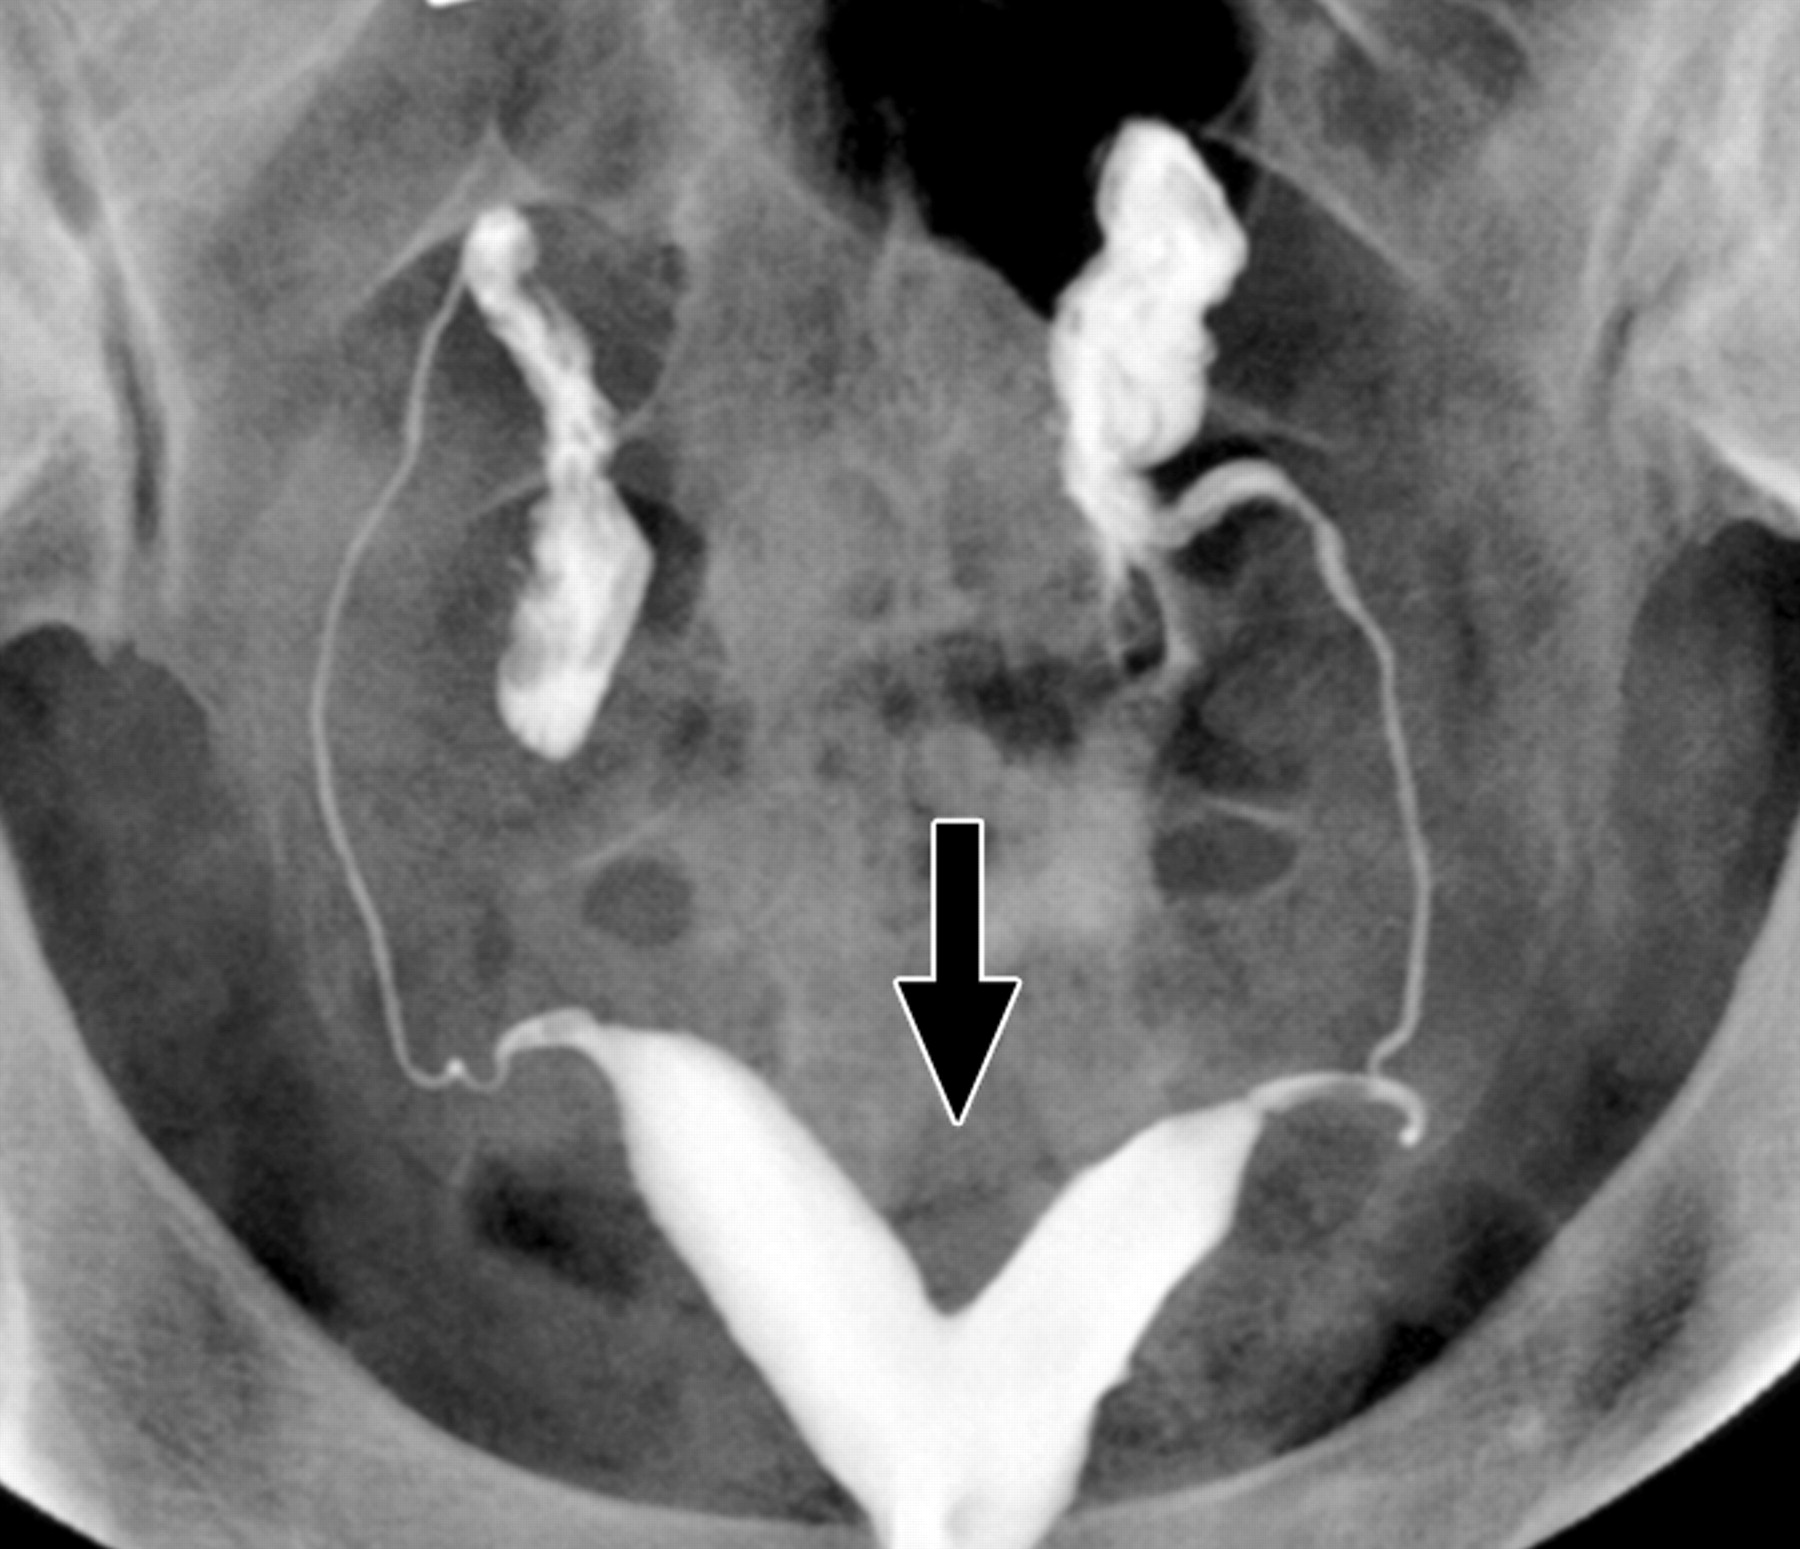

Histerosalpingografi (HSG) veya Türkçe deyişle rahim filmi jinekolojide rahim içinin ve kanalların yapısal ve işlevsel özelliklerini incelemede kullanılan bir yöntemdir. İnfertilite (kısırlık) değerlendirmesinde istenen temel testlerden birisidir. Yandaki resimde normal bir rahim şekli ve her iki kanaldan ilacın kolayca geçip karın boşluğuna dağıldığı normal bir film görülmektedir. Ayrıca rahim ağzına veya rahme uygulanan bir müdahale sonrasında (kürtaj gibi) adet kanamalarının kesilmesi ya da çok azalması durumunda rahim ağzı kanalındaki muhtemel bir tıkanıklığın veya rahim içersindeki muhtemel bir yapışıklığın (Asherman sendromu) değerlendirilmesinde, tekrarlayan düşüklerde rahimde doğumsal bir gelişim kusuru bulunup bulunmadığının (aşağıda soldaki resim - bölmeli rahim) belirlenmesinde de yaygın olarak kullanılır.